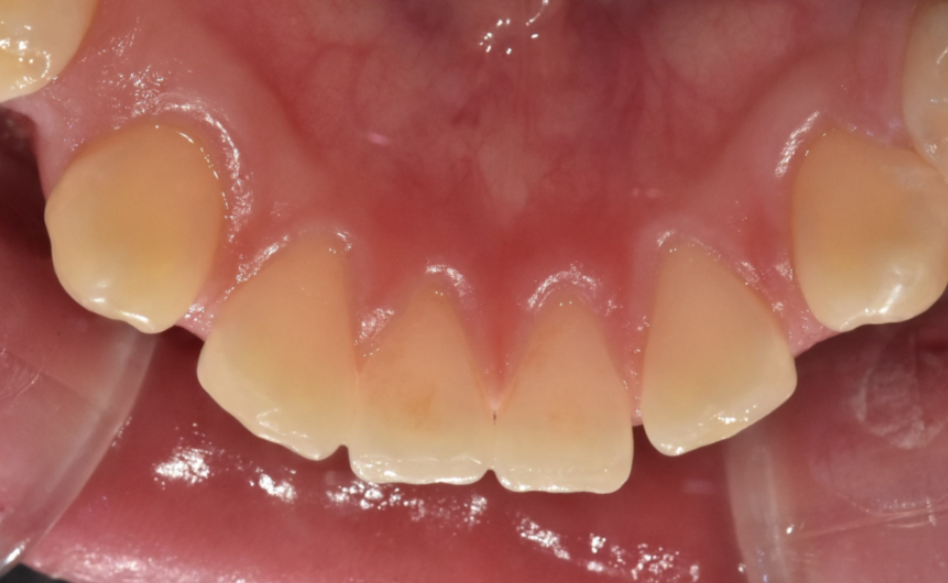

가운데 치아가 눈에 띄게 벌어져있는 환자분

앞니끼리 벌어진 공간이 좁을 경우는

레진이라던가

라미네이트, 크라운과 같은 보철로도 메울 수가 있습니다.

대신 메운 공간만큼 치아 사이즈가 커지는 단점이 있겠죠.